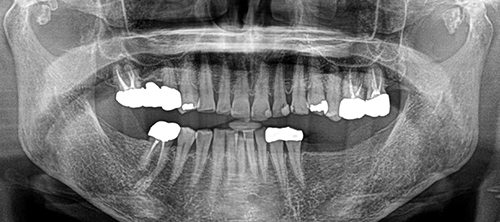

治療内容 ・インプラント

・セラミック修復

治療期間 9ヶ月

治療費用 250万円

治療経過 全体的に歯が磨耗し、下顎奥歯には義歯が装着されていたが義歯は破損し使えていない状態であった

今回奥歯でしっかり咬めるようにしたいということで欠損部にはインプラント治療を、少しでも清掃性を良くしたいという目的でセラミック修復を希望された。

元々全体的に歯と歯の間がすいていて食渣が挟まりやすかったが、インプラントを入れることで奥歯にしっかりしたサポートが回復され、歯の隙間が自然と詰まり、物詰まりも軽減することができた。

Before